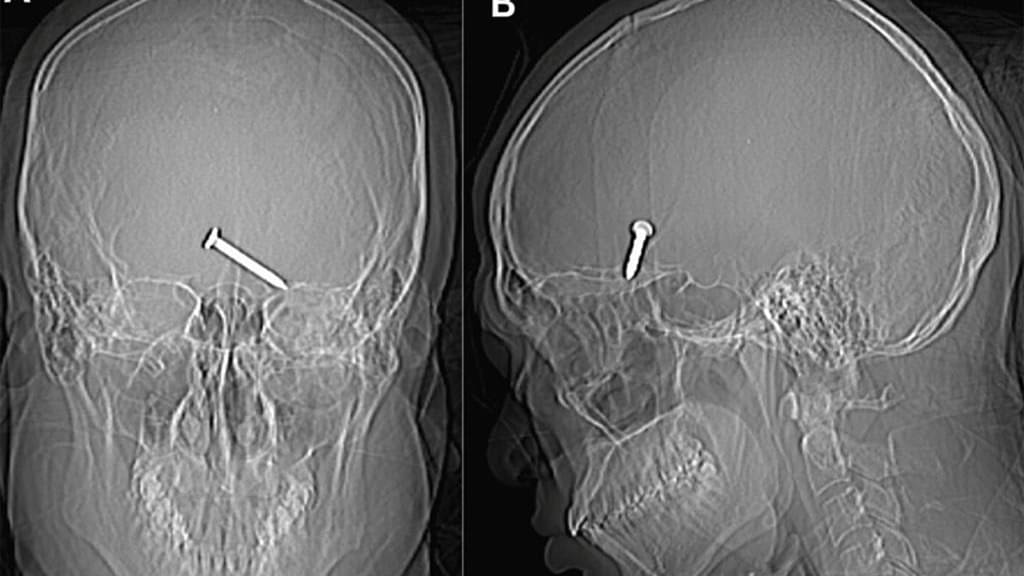

Stunning X-ray images reveal a 3.2 cm nail deeply lodged in the frontal lobe of the man's brain which is a critical region for movement and speech. The bleeding had extended to other areas of his brain. The study, published in the medical journal, reports wounds at the lateral canthus of the left eye where the two eyelids meet, along with fractures of the left orbital roof and floor. Remarkably, the nail managed to avoid crucial arteries and nerves, sparing the man from any enduring damage, as indicated in the study.